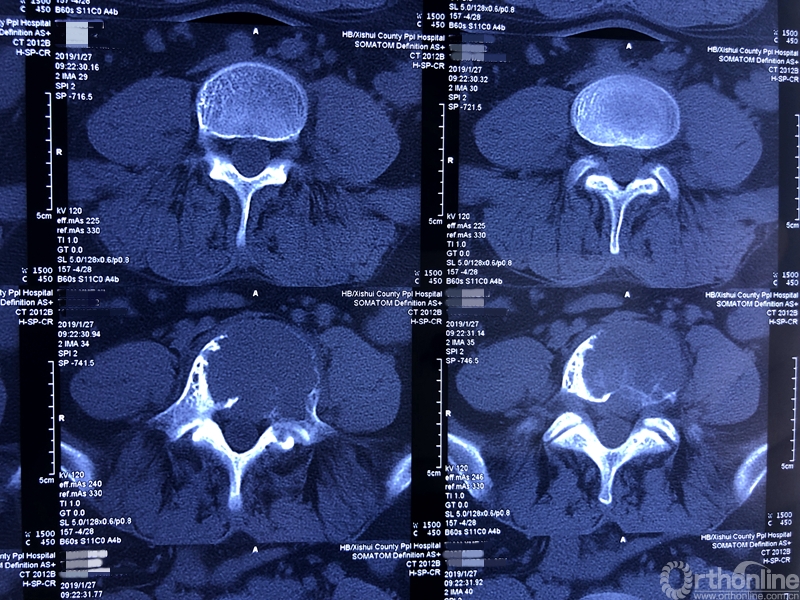

据介绍,患者为39岁男性,在一年前开始出现腰部反复疼痛的症状,休息下后疼痛还可以缓解,当时并未引起患者重视。过年后感觉疼痛加重,赴当地医院检查。核磁共振显示腰椎上长了一个鹅蛋大小的肿瘤,不偏不倚地侵蚀在第五节腰椎上,正是腰椎和骨盆连接部位附近。于是患者来同济医院骨科就诊。

就诊前CT

通过对患者详细的身体检查、穿刺活检和综合评估后,确诊患者是腰椎骨巨细胞瘤,第五腰椎破坏70%以上,邻近软组织也有破坏。这种肿瘤属于交界性的有恶性倾向的良性肿瘤,若不彻底切除,患者疼痛会逐渐加剧,甚至因骨质坍塌而瘫痪,若肿瘤细胞转移更会危及生命。若是能在早期尽快彻底、完全地切除肿瘤及被侵蚀椎体,病人才很可能完全战胜肿瘤。